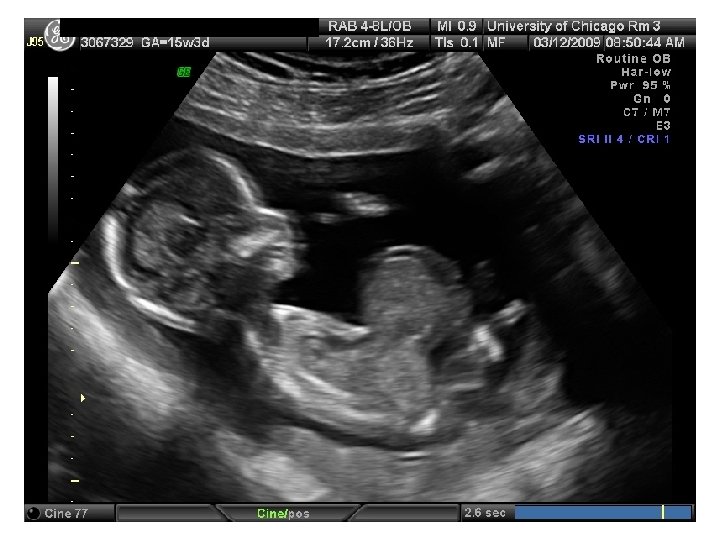

QUIZ What is Your Diagnosis? Case: Patient J. F. 30 years old, at 32 week gestation. Presented with the following pictures.

Answer: a) Trisomy 21 b) Non-immune Hydops c) Paravo virus Infection